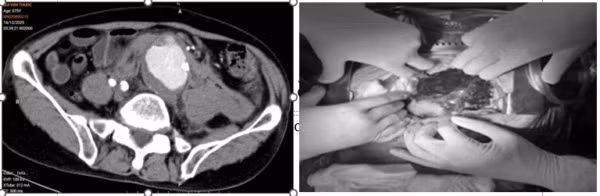

Người bệnh nam, 75 tuổi, nhập viện lúc nửa đêm trong tình trạng đau bụng dữ dội, huyết động không ổn định. Qua thăm khám lâm sàng và hình ảnh chụp cắt lớp vi tính (CLVT), các bác sĩ xác định người bệnh bị vỡ phình động mạch chủ bụng kèm khối máu tụ lớn trong ổ bụng, đe dọa trực tiếp đến tính mạng.

Hình ảnh khối máu tụ do vỡ động mạch chủ bụng trên phim chụp CLVT và sau khi mở bụng - Ảnh BVCC